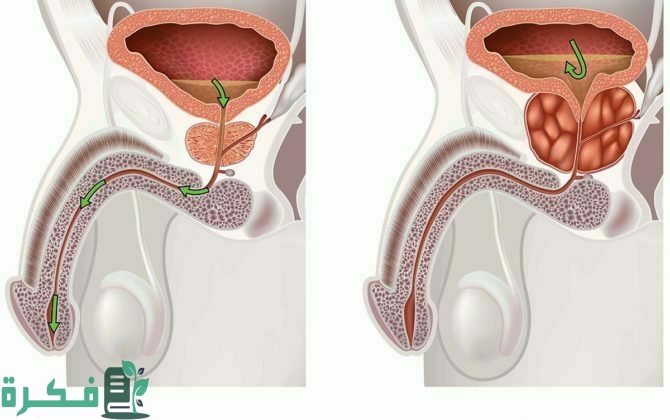

أكمل القراءة »أفضل 5 أدوية علاج تضخم البروستاتا سنتعرف عليهم من خلال هذا المقال، حيث يعد تضخم البروستاتا أحد الأمراض المزعجة المنتشرة،…